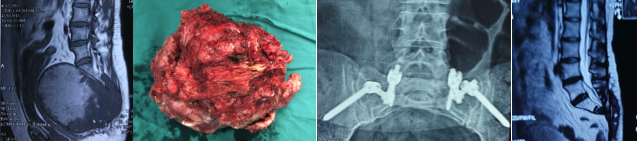

骶骨巨大脊索瘤